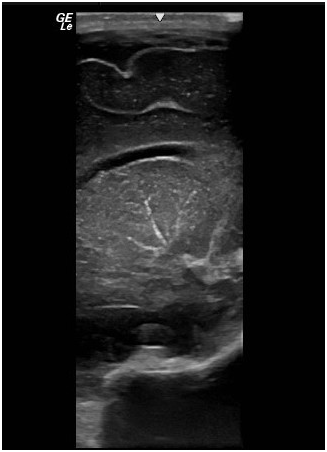

Initial full blood count showed mild thrombocytopenia of 101,000/mm3. Platelet count decreased gradually to the lowest value of 37,000/mm3 at the age of one week. Then, the number gradually improved back to normal at 314,000/mm3 without intervention at the age of 2weeks. Cranial ultrasonography revealed bilateral linear echogenic streaks at the basal ganglia, suggestive of lenticulo striate vasculopathy (Figure 3). Abdominal ultrasonography showed borderline hepatosplenomegaly but no ascites. Blood chemistry tests including urea, electrolytes, creatinine; liver function tests; and bone profile were all within normal limits. The STORCH profile was negative. At the age of 5 days, atropine injection was administered without improvement of heart rate, and furosemide was commenced in view of development of signs of heart failure clinically and by echo assessment. In the next week, there was progressive increase in respiratory distress with further enlargement of cardiac chambers, and the decision for cardiac pacing was planned. Permanent Medtronic bipolar epicardial pacing leads were implanted on the right ventricle. Pacing leads were connected to St. Jude Microny 2 pacemaker pulse generator placed in a pocket created below the rectus sheath in the left upper abdominal quadrant (Figure 4). Parameters were checked and paced at the 100bpm VVIR mode. The infant was clinically stable after pacing with improvement of respiratory and cardiac function. Repeated ECG showed stable heart rhythm and rate at 100bpm (Figure 5). She was gradually weaned to room air 5days after surgery and discharged home one week later with stable hemodynamic status. Upon follow-up in the outpatient clinic till the age of one year, she was developmentally normal and gaining weight and had normal cardiac functions.

Figure 3 Cranial ultrasonography shows linear echogenic streaks at the basal ganglia suggestive of lenticulo-striate vasculopathy.